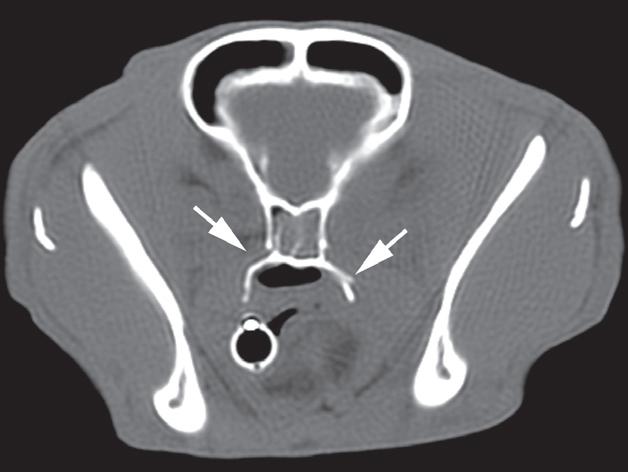

(b) CT+C, TP Badanie wykonano u 8-letniej, kastrowanej samicy jamnika z potwierdzoną nadczynnością kory nadnerczy zależną od przysadki. Ryciny a i b to reprezentatywne obrazy w płaszczyźnie poprzecznej na poziomie przysadki. Rycina c jest powiększonym obrazem dołu przysadki. W badaniu bez podania środka kontrastowego (a) uwidoczniono słabo odgraniczoną, częściowo zmineralizowaną masę zlokalizowaną w okolicy przysadkowo-podwzgórzowej. Masa uległa jednorodnemu wzmocnieniu kontrastowemu i miała wymiary 11 mm (wysokość) na 10 mm (szerokość). Dane z wywiadu, objawy kliniczne oraz wyniki testu hamowania małą dawką deksametazonu wskazywały na zależną od przysadki nadczynność kory nadnerczy